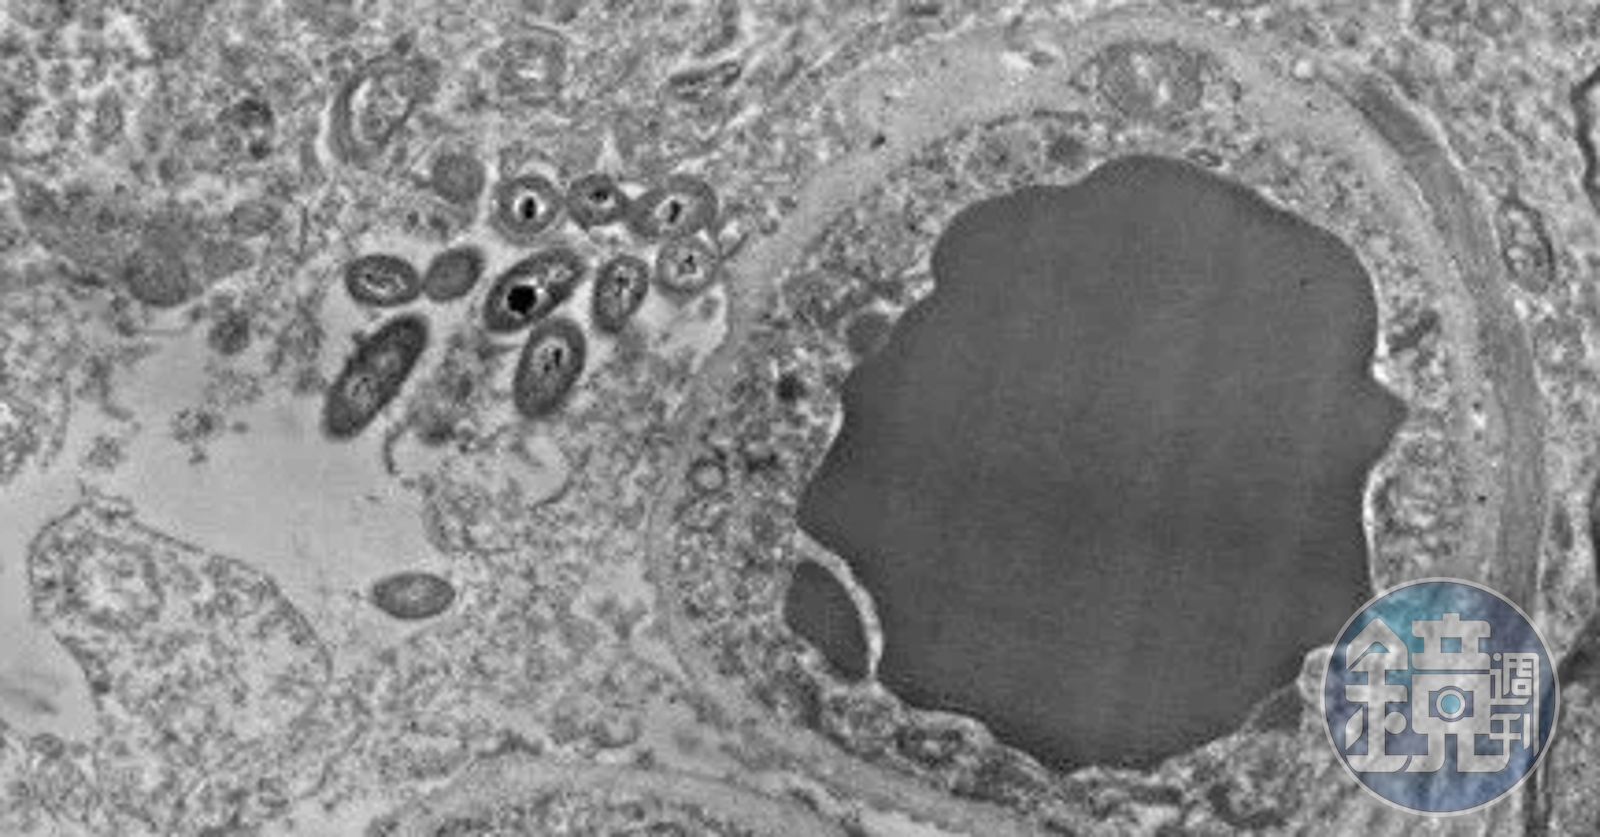

通過對電子顯微照片的最初調查,Roberts團隊觀察到,常駐細菌存在一些莫名的偏好。這些細菌似乎棲息在星形細胞中,這種星形細胞又被稱為星形膠質細胞,可與神經元相互作用並支持神經元。值得注意的是,大腦內的微生物主要聚集在星形膠質細胞的末端和周圍,而星形膠質細胞則常位於血腦屏障處,包圍著血管。此外,在被稱為髓磷脂的脂肪物質包裹的神經元周圍,也有很多「腦微生物」富集。目前,Roberts還無法對這些偏好進行解釋,但她懷疑這些細菌可能受到了腦細胞中的脂肪和糖的吸引。

她的實驗室通過檢查死後數小時內保存的腦組織切片來尋找健康人和精神分裂症患者之間的差異。大約在5年前,當時是Roberts實驗室本科生的神經科學家Courtney Walker發現這些切片的精細圖像中存在不明桿狀物,並開始對其著迷。Roberts之前也見過這些「桿狀物」。「但由於我在尋找其他的東西,就把它們拋在一邊了」,她說。

但是Walker是對於這些桿狀物很是癡迷,漸漸地,Roberts也開始向UAB的同事們諮詢一些意見。就在今年,一位細菌學家給了她一個出人意料消息:這些桿狀物是細菌。目前,他的團隊已檢查過的34個大腦中都發現了這種細菌,在這34個大腦中,健康人腦和精神病患者大腦各占一半。